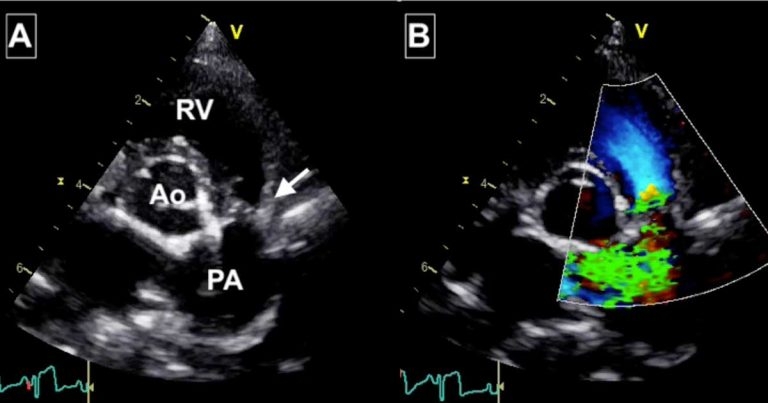

Figure 1. Images from Toby’s echocardiogram. (A) The arrow points at the stenotic lesion and shown fused thin valve leaflets. Post-stenotic dilation of the main pulmonic artery is evident distal to the valve. Abbreviations: Ao = aorta, PA = pulmonary artery, RV = right ventricle. (B) The colour Doppler image shows turbulence (green) originating from the fused valve, explaining the audible heart murmur.

Toby was referred to a cardiology specialist and Doppler echocardiography was performed. Severe hypertrophy of the right ventricular free wall and interventricular septum existed, which was considered secondary to malformation of the pulmonic valve. This consisted of fused, but thin and mobile valve leaflets consistent with the diagnosis of pulmonic stenosis (Figure 1).